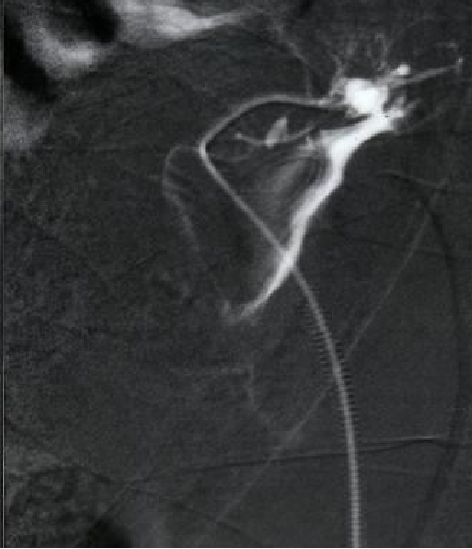

肾活检穿刺有时会伤及肾外动脉导致致命出血 年轻女性,急性肾功能衰竭(goodpasture syndrome),需要紧急活检。共穿刺5次。超声探及肾周血肿,血压下降需要输血。紧急血管造影

(Super)selective embolization is a method of choice in treatment of postbioptic kidney complications